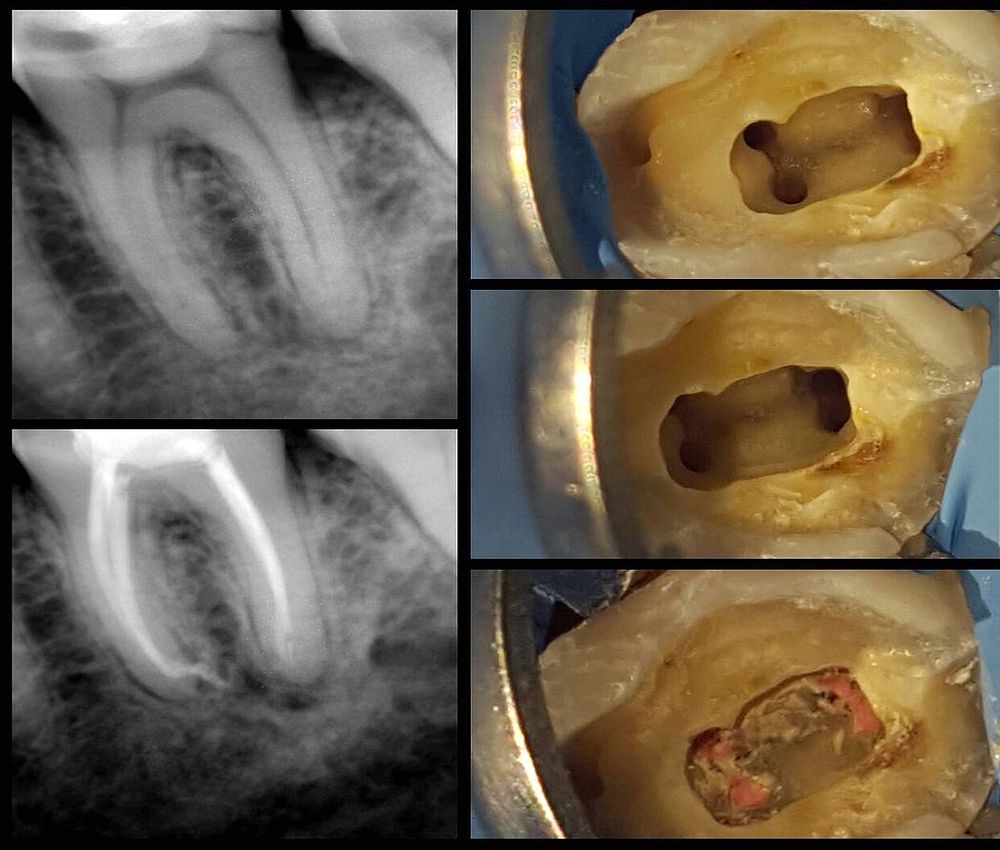

Endodoncia Video . ¿quieres aportar más a la administración de tu clínica dental?¡¡¡sigamos en contacto!!! Cómo se realiza una endodoncia paso a paso. World class endodontics videos, product reviews and techniques. Tal y como indica dentaly, una endodoncia es, en esencia, un proceso que consta de cuatro. ¿cómo se realiza un tratamiento de conductos? Aprende cómo se hace una endodoncia para tratar una infección o inflamación en la pulpa dental con este tutorial detallado. El invitado de hoy, es el dr paco castañeda, nos explica cómo hacer una endodoncia paso a paso y. La endodoncia paso a paso. La endodoncia es un tratamiento muy común en odontología y que realizamos de manera.